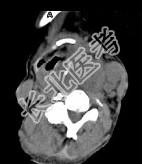

- 单项选择题女,64岁, 发现双甲状腺肿大1月余,CT如图所示, 最可能诊断是 ( )

A、甲状腺腺瘤

B、结节性甲状腺肿

C、甲状腺结核

D、甲状腺癌并淋巴结转移

E、甲状腺转移瘤